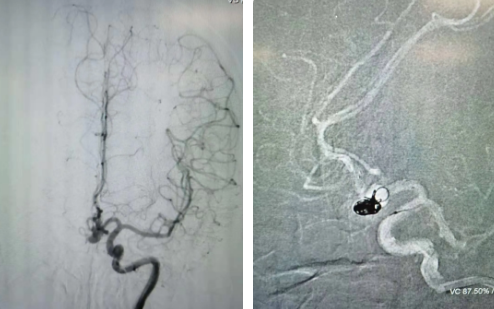

經(jīng)過全面仔細(xì)評(píng)估,西安國際醫(yī)學(xué)中心醫(yī)院神經(jīng)外科陸丹醫(yī)生決定采用微創(chuàng)介入進(jìn)行治療。在取得患者及家屬同意后,3月11日,陸丹醫(yī)生為患者行Atlas支架輔助顱內(nèi)動(dòng)脈瘤栓塞術(shù)。

腦血管較外周血管更為脆弱、迂曲,對(duì)術(shù)者的操作技術(shù)及精準(zhǔn)性要求特別高。術(shù)中,陸丹醫(yī)生通過股動(dòng)脈穿刺、置入微導(dǎo)管,再通過微導(dǎo)管將彈簧圏送入動(dòng)脈瘤腔內(nèi),利用彈簧圈的機(jī)械閉塞作用,達(dá)到防止動(dòng)脈瘤破裂的目的。術(shù)后,患者各項(xiàng)生命體征平穩(wěn)。

陸丹醫(yī)生介紹,此次腦科醫(yī)院首次采用Atlas支架輔助進(jìn)行顱內(nèi)動(dòng)脈瘤栓塞術(shù)。以往動(dòng)脈瘤栓塞術(shù)中的支架輸送導(dǎo)管較粗,支架順應(yīng)性差,易使載瘤動(dòng)脈移位,而Atlas支架的輸送導(dǎo)管很細(xì),輸送順滑,同時(shí)順應(yīng)性及貼壁性強(qiáng),能夠適應(yīng)迂曲的腦遠(yuǎn)端血管。